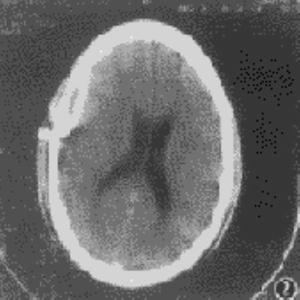

1.顱腦CT掃描

典型表現為大腦凸面,顱骨內板下可見範圍廣泛的新月形低密度區,CT值早期一般在0~16Hu,鄰近腦組織可見廣泛水腫,占位效應顯著,中線結構移位,累及雙側者中線結構移位可不明顯。CT增強掃描,可見邊界清楚,厚度均勻的細強化帶,相對的腦表面呈腦回狀強化,膿腫內緣的強化帶密度不均勻,厚度不規則,以縱裂為主要範圍的硬腦膜下膿腫,多為梭形。